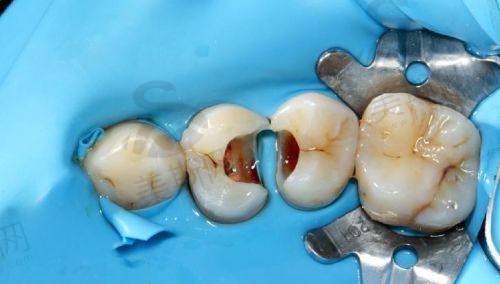

6. 口腔综合治疗:涵盖洗牙(超声波洁牙 + 喷砂抛光)、补牙(树脂充填、玻璃离子充填)、拔智齿(微创拔除阻生齿)、根管治疗等基础项目,医疗保险报销比例达50%-80%。